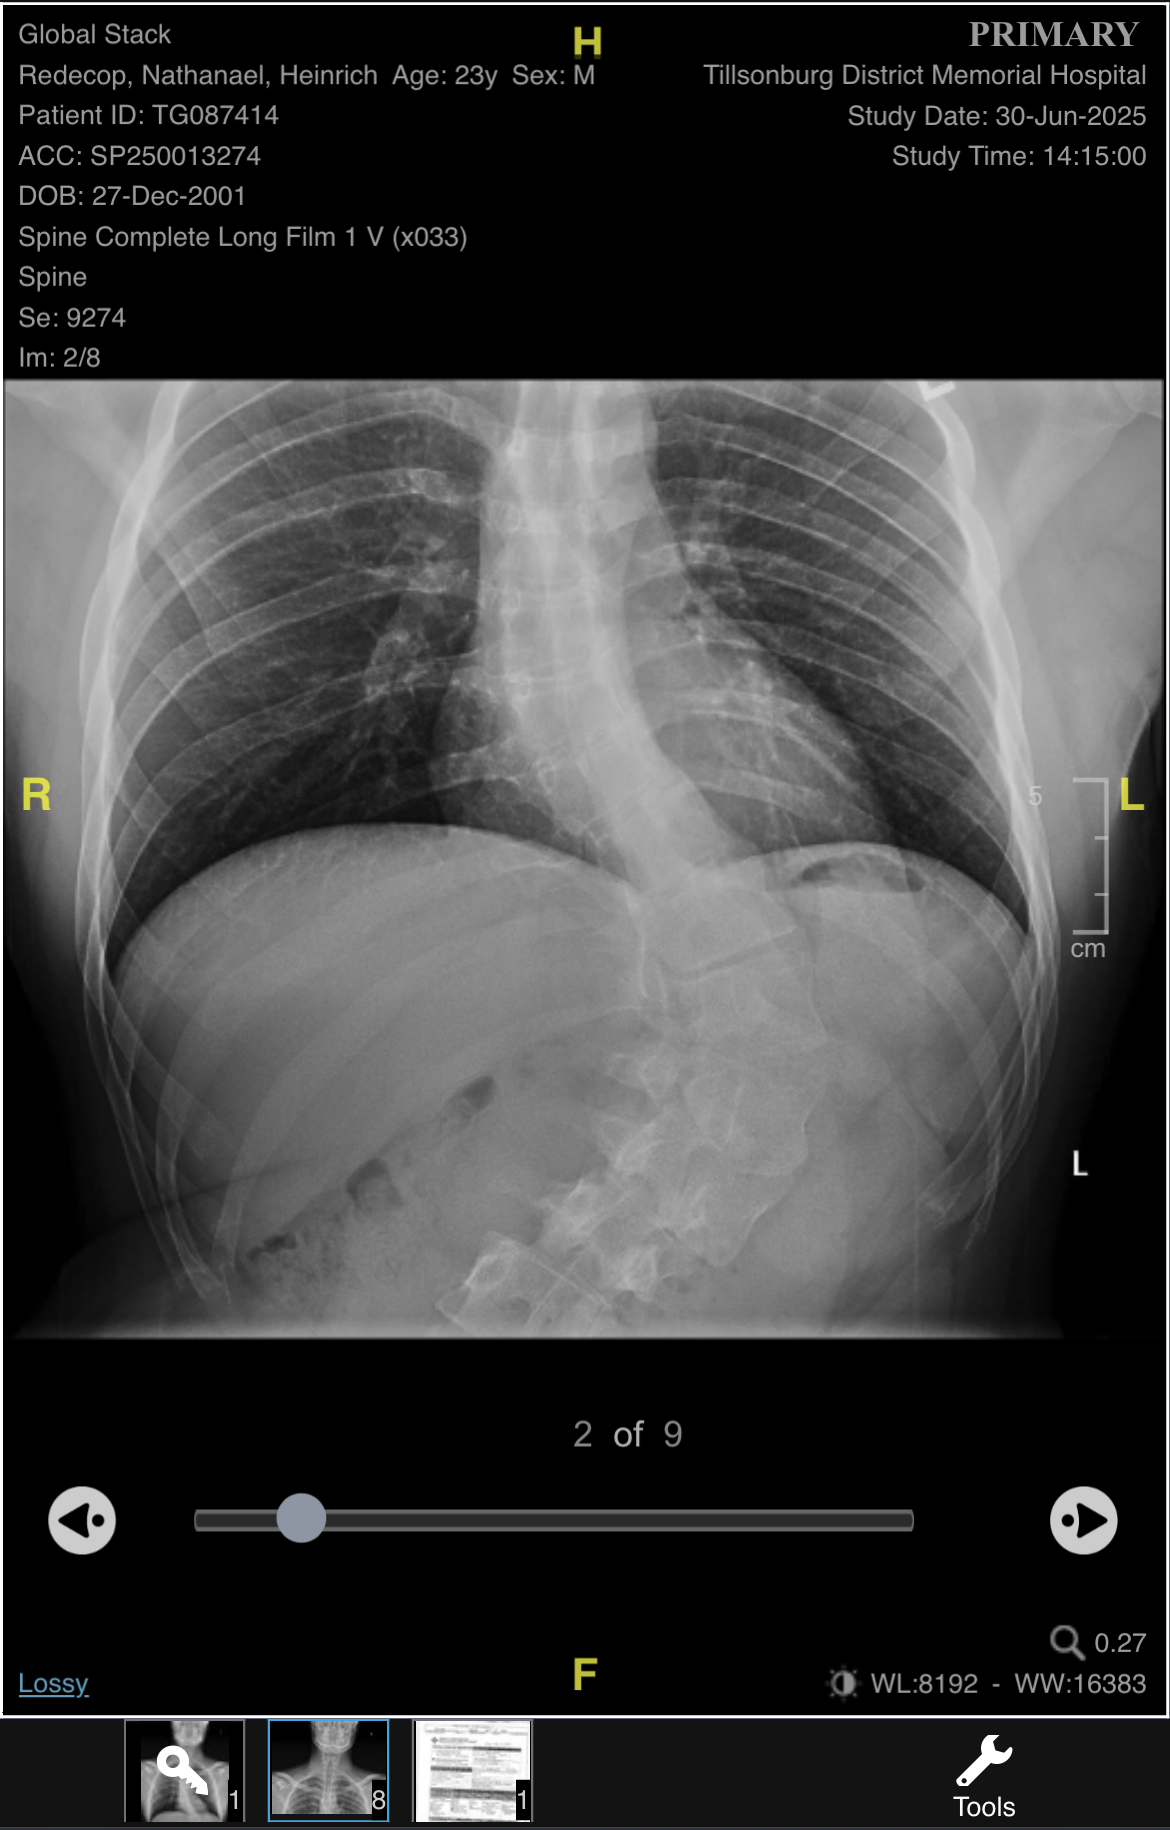

Hello. This is my nephew Nathanael Redecop. He is 24 years old and has been living with severe scoliosis. As you can see in the photo, the curve in his spine has progressively worsened to 68 degrees. He is unable to sit or stand for long periods of time. Laying flat on his back gives him the least amount of pain.